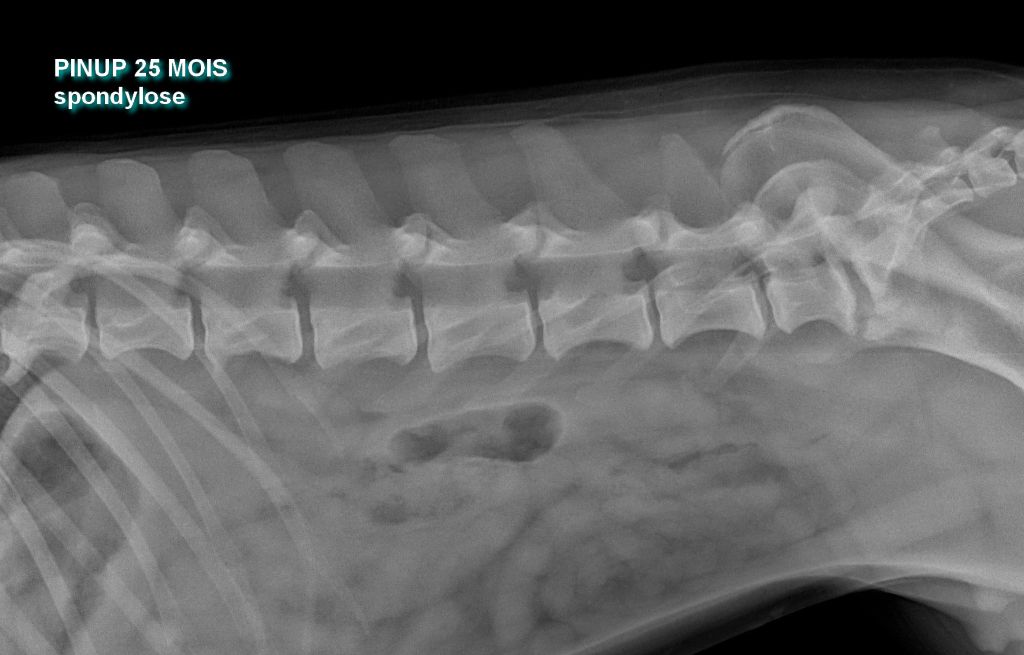

ADN : compatible ASO /PSO : indemne de cardiopathie HD B : indemne de dysplasie Spondylose : Spd0 non officiel dysplasie rénale par echographie : indemne |